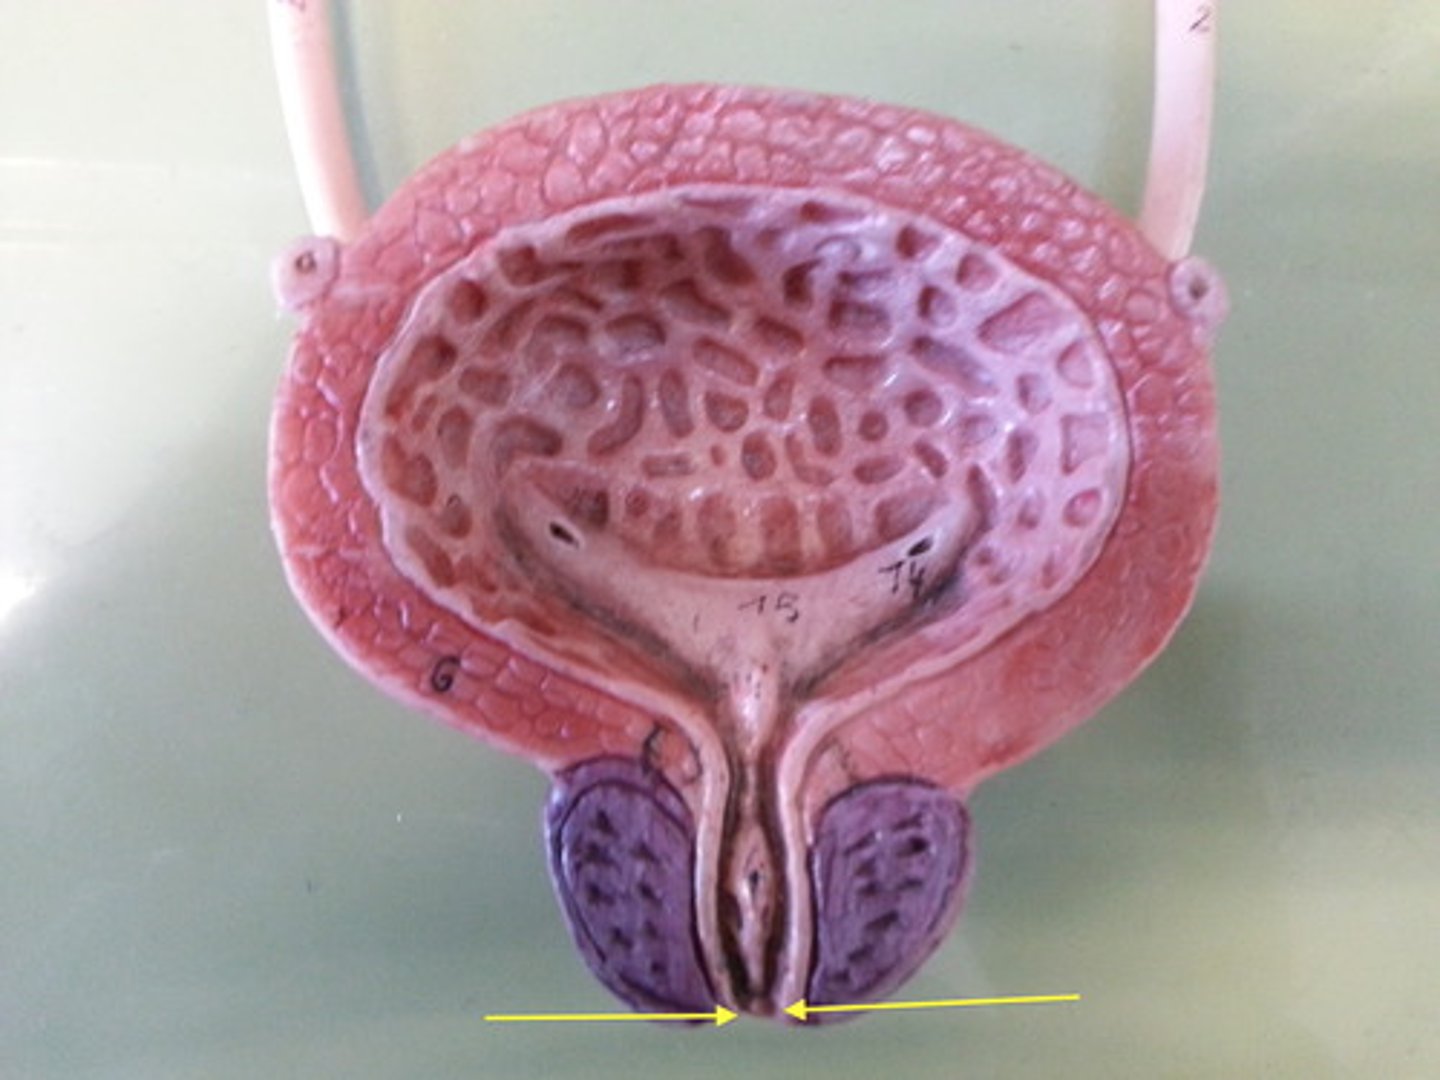

urinary bladder

urinary bladder

detrusor muscle

layer

internal urethral sphincter

bladder neck

external urethral sphincter

ureteric orifice

trigone of bladder

rugae

Urethra